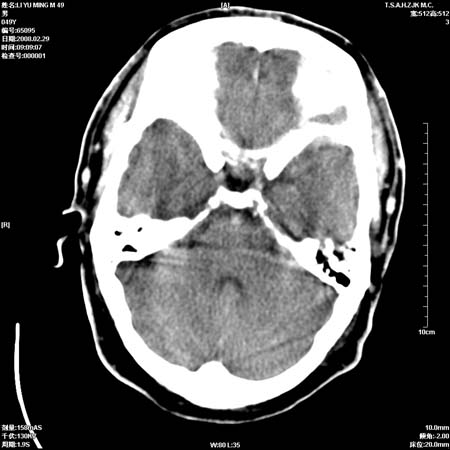

一周后复查ct:

可能为正常。间隔一周蛛血应基本吸收;再过一周复还是这样应该可以肯定了。

一周时间密度未见改变,考虑为正常图像(脑动脉硬化?)。